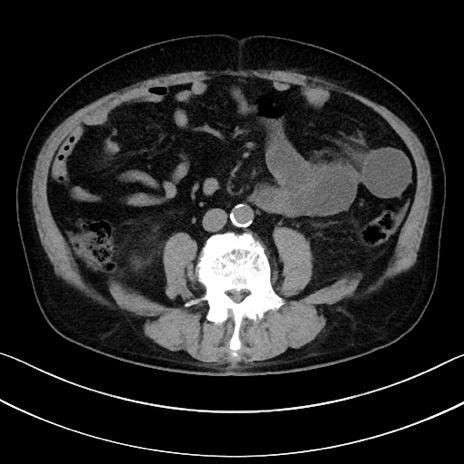

症例15(横断像)

【症例】70歳代男性

【主訴】腹痛

【現病歴】今朝から腹痛あり。全体的に痛い。特に左上の方。排ガスが今日はない。冷や汗が出る。

【既往歴】直腸癌術後

【身体所見】左側腹部〜上腹部に圧痛あり。腹膜刺激症状明らかなではない。軽度反跳痛。左下腹部に術後瘢痕あり。

【データ】WBC 7700、CRP 0.02